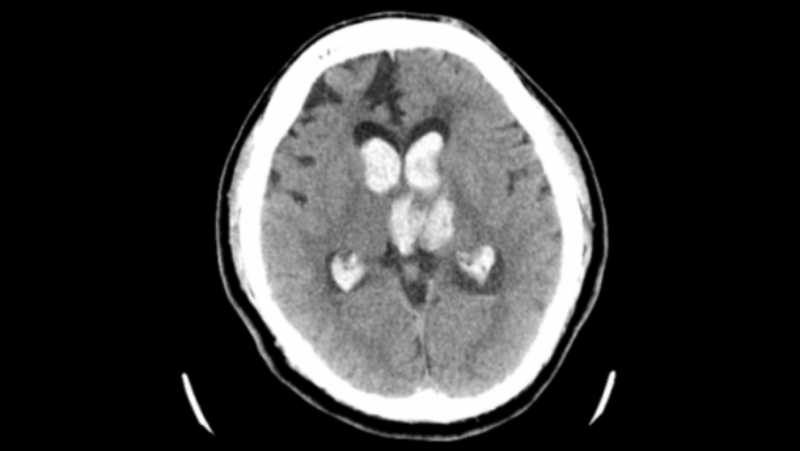

醫(yī)生團隊在患者頭上畫好線,找準位置錐顱,置管進入,有淡紅色的血水從管子里流出來。固定好引流管后,連接上引流裝置。隨后根據(jù)腦里血腫的情況,每天往里面打一到兩次尿激酶,每次用的量在 5000 單位到 20000 單位不等。一直到血腫基本清除了,才把引流管拔掉。

尿激酶溶解血腫第四天